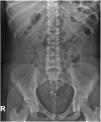

We present the case of a patient aged 14 years assessed in the emergency department for colicky pain in the right flank radiating toward the hypogastrium. The urinalysis was normal, and since the presentation was compatible with renal colic, an abdomen radiograph was performed (Fig. 1).

Ovarian tumours are rare in children, amounting to 1% to 5% of total paediatric tumours. Up to 90% of paediatric ovarian tumours are germ cell tumours, and the most frequent type is mature cystic teratoma (55%–70% of ovarian tumours in paediatrics).1,2 Ovarian mature cystic teratomas are benign tumours that can develop at any age, but the incidence peaks in the second and third decades of life. They arise from at least 2 of the 3 germ layers, and the contents are most frequently of ectodermal origin (hair, fat, teeth, skin…).2 Most patients are asymptomatic at diagnosis, with detection of the teratoma as a chance finding, but patients may develop abdominal pain, a palpable mass, complications such as ovarian torsion or rupture and even paraneoplastic syndromes, although the latter is very rare. Up to 10% of paediatric cases are bilateral.3 The initial diagnosis is made by abdominal ultrasound, in which the most common appearance is a cystic lesion with posterior shadowing (Rokitansky nodule). The evaluation is usually completed with an MRI scan to measure the mass more accurately and determine its relationship with adjacent structures.2 Approximately 50% have calcifications and up to 22% contain teeth detectable by imaging.4 Therefore, the detection of features with calcification density or shaped like a tooth in an abdominal X-ray may be key in the diagnosis of teratoma.